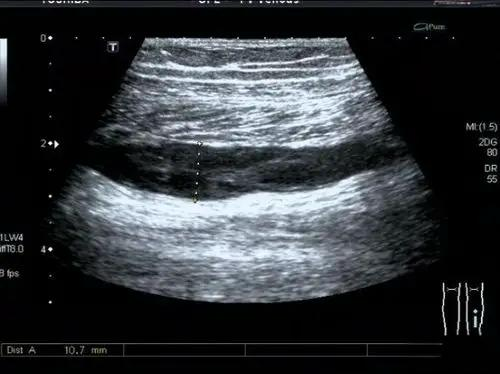

五、下肢静脉彩超检查针对下肢深静脉血栓的优势

下肢静脉彩超检查是一种重要的诊断工具,对于及时发现并处理下肢静脉相关问题具有很高的临床价值。通过超声波成像,医生可以清楚地观察到深静脉内的血栓情况,确定病变的程度和位置,后续的诊断和治疗提供依据。通过定期检查,医生还可以观察深静脉血栓的变化情况,判断治疗是否有效,以及是否需要调整治疗方案。对于住院病人,特别是那些长时间卧床或缺乏活动的患者,下肢深静脉超声检查可以帮助及早发现潜在的血栓形成,并采取相应的预防措施,避免严重的并发症如肺栓塞发生。